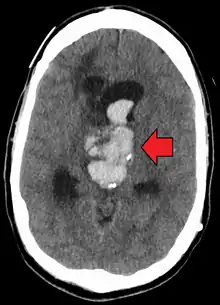

| Axial CT scan of a spontaneous intracranial hemorrhage | |